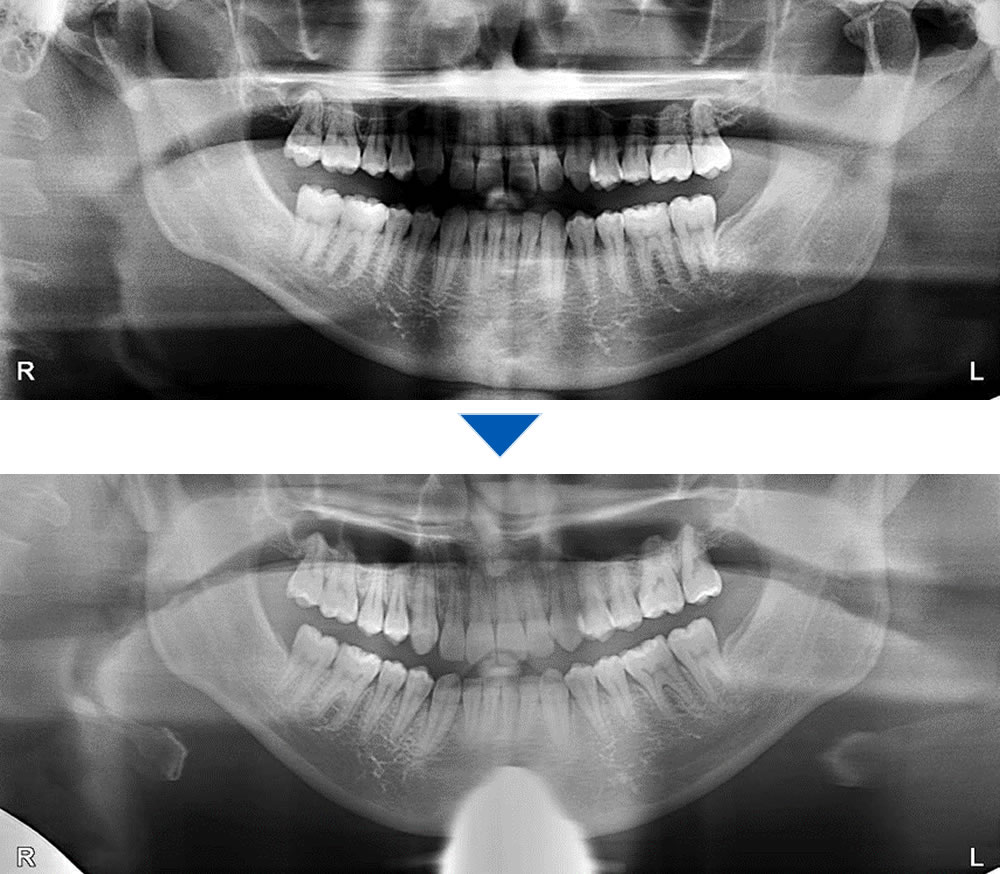

レントゲンの比較

離れていた歯間が閉じて、キレイに排列されました。